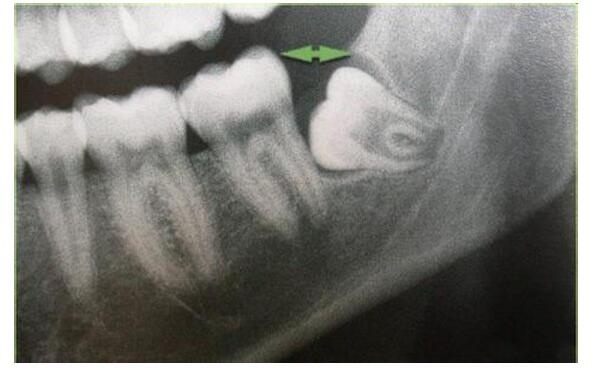

深圳牙科醫院醫生介紹,智齒一般在成年後不定時萌出,由於(yu) 位置太過靠後,所以智齒多出現阻生或位置不正的情況,比較容易殘留食物殘渣,不好清潔,會(hui) 經常引發智齒周圍組織炎症,而且還會(hui) 造成智齒和鄰牙蛀牙,所以建議這種情況,可以盡早拔除。

一般情況下,除非是智齒萌出位置很正,沒有影響到鄰牙的健康,也沒有引起智齒周圍組織的炎症,而且還有對咬牙,這種可以先觀察,暫時保留,並注意口腔衛生,適用小刷頭牙刷刷牙。其他的一般經常發炎引起疼痛的,或者是侵犯鄰牙,導致牙齒畸形的,或者是導致鄰牙蛀牙的,都建議進行拔牙。